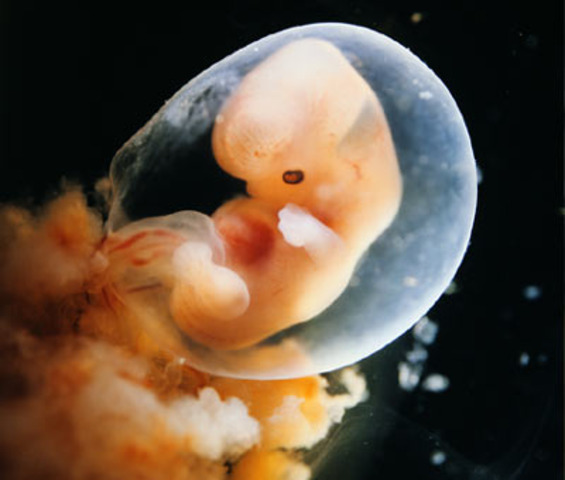

• 12 weeks

12 weeks

nerve cells are multiplying rapidly, and in your baby's brain, synapses are forming furiously. His face looks unquestionably human: His eyes have moved from the sides to the front of his head, and his ears are right where they should be. From crown to rump, your baby-to-be is just over 2 inches long (about the size of a lime) and weighs half an ounce.

http://www.babycenter.com/6_your-pregnancy-12-weeks_1101.bc